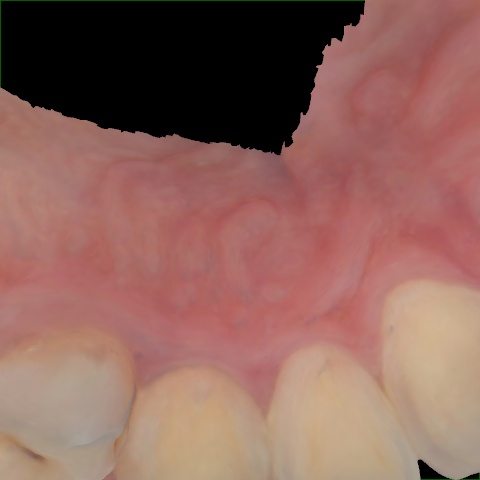

NHD39990

Annotated as "Good"